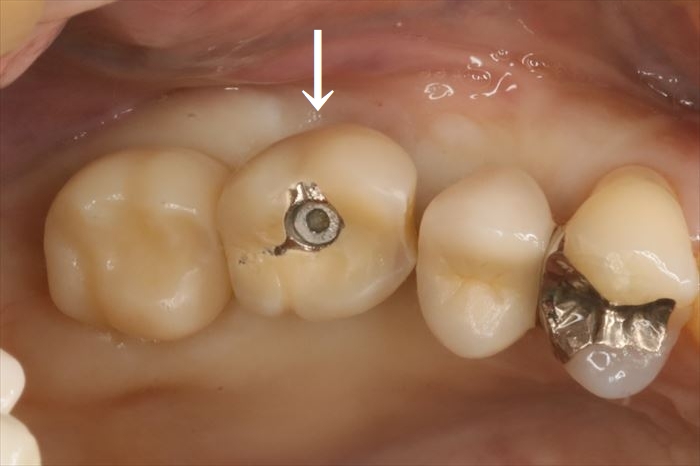

N・Hさんの右上第一大臼歯部分(6┘:右上6)のインプラントの再治療を行います。(矢印)

画像左端の右上第二大臼歯部分のインプラント埋入オペ時のデンタルレントゲン写真です。

丸印が本日撤去するインプラントです。

インプラントネック部分が骨吸収を起こしています。

咬合面のスクリューを緩め、まずは被せ物(クラウン)を取り外しました。

インプラント本体が理想的な位置よりも頬側に存在していることがわかります。